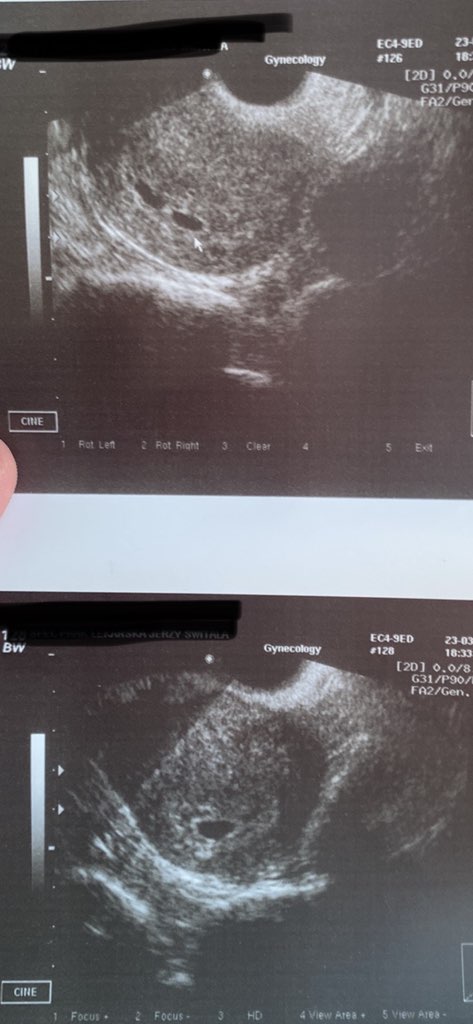

jeśli chodzi o ciąże bliźniacze to ja miałam pierwsze usg 23 marca(zdj z dwoma pęcherzykami) tydz później, bo wariowałam na sama myśl o bliźniakach poszłam na NFZ do ginekologa zrobić usg i był jeden pęcherzyk. Także mam nadzieje ze jest jedno 🙈🤣

• IMG_0185.jpg

IMG_0185.jpg

65,5 KB · Wyświetleń: 86

• IMG_0267.jpg

IMG_0267.jpg

161 KB · Wyświetleń: 101